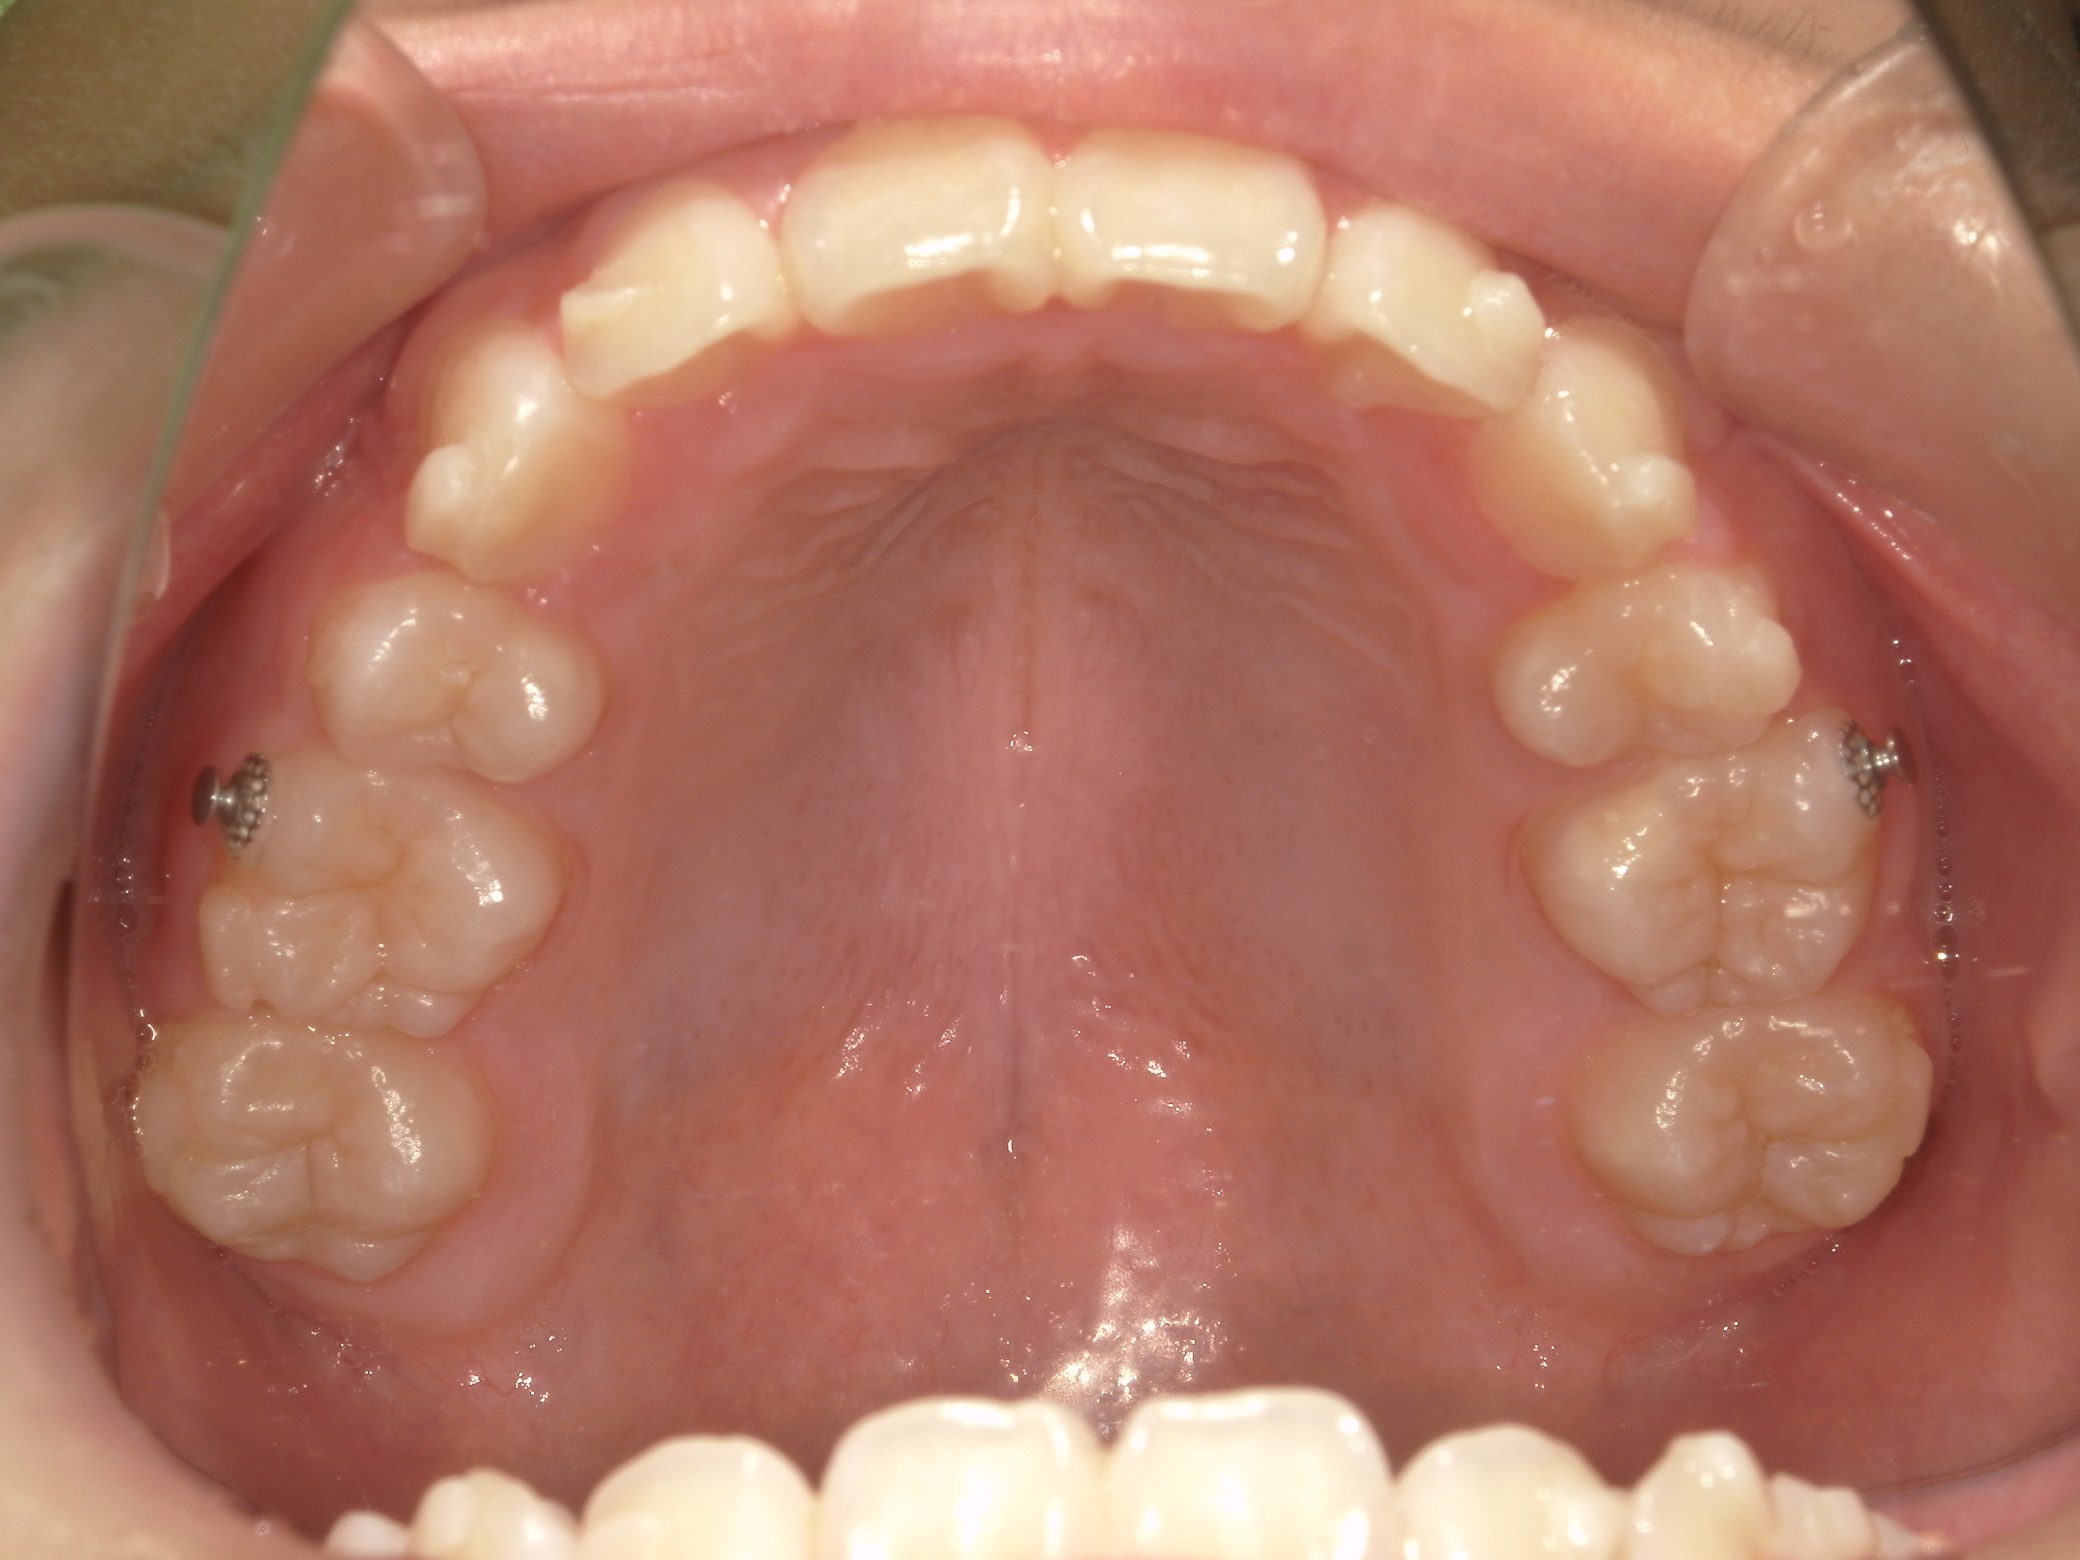

【小学生】インビザラインフル 叢生(でこぼこ)と 上顎前突(出っ歯)を改善

Before

After

八重歯と上顎前突(出っ歯傾向)が気になるということで来院

上下4本の歯を抜歯して矯正しました

しっかり装着してくれたので3年はかかると予測していましたが、1年半で終了しました

咬み合わせも改善し満足してくれました